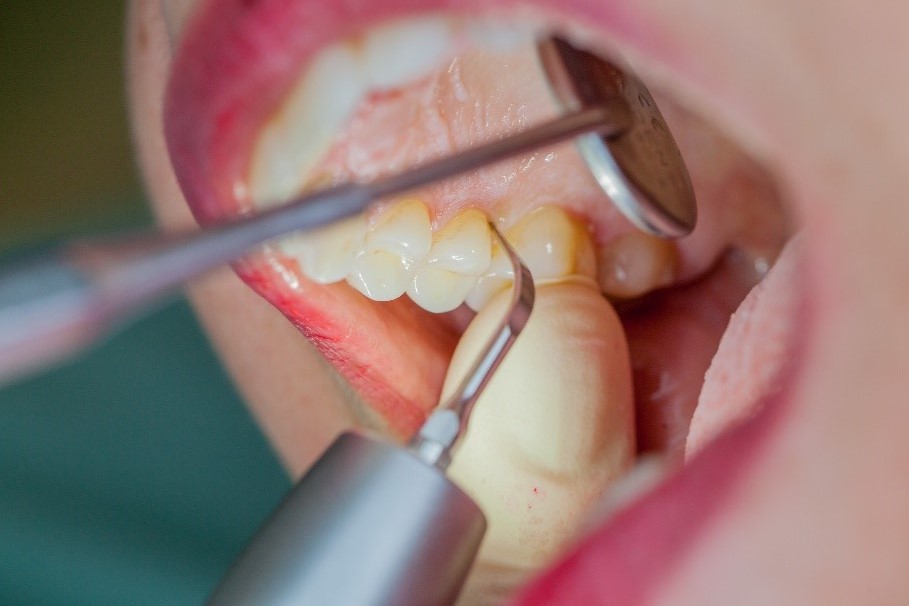

Where necessary, initial periodontal treatment is carried out. First, professional tooth cleaning establishes healthy gingival conditions. In this procedure, calculus (Fig. 1) and biofilm (Fig. 2) are removed as far as the gingival sulcus. In combination with careful instruction on oral hygiene, this gives the patient the basis for long-term freedom from inflammation.15

Removal of subgingival coatings (debridement) is carried out using sonic or ultrasonic devices and special periodontal tips as initial periodontal treatment (Fig. 3). Manual instruments can also be used. Further surgical and/or regenerative measures may be necessary, depending on the situation.